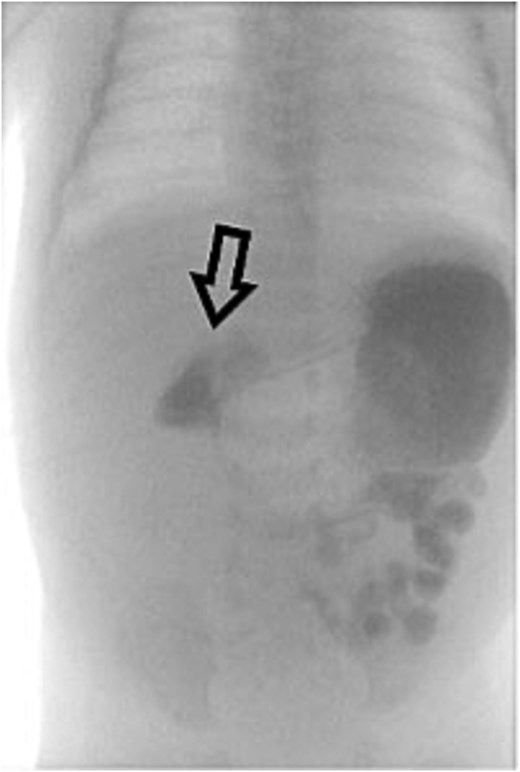

On Day 3 of life, she developed multiple episodes of bilious emesis and passed meconium-stained stools. An abdominal radiograph revealed gas-filled, non-distended bowel loops on the right and absence of small bowel gas on the left (Fig. 1), raising suspicion for malrotation. An upper GI (UGI) series confirmed abnormal duodenal positioning and obstruction, suggestive of malrotation with volvulus (Fig. 2). Emergent Ladd’s procedure was performed, revealing midgut volvulus with cloudy peritoneal fluid but viable bowel.

Abdominal X-ray shows nonspecific gas pattern with gas-filled, nondistended bowel loops on the right. Absence of small bowel gas on the left raises suspicion for malrotation.